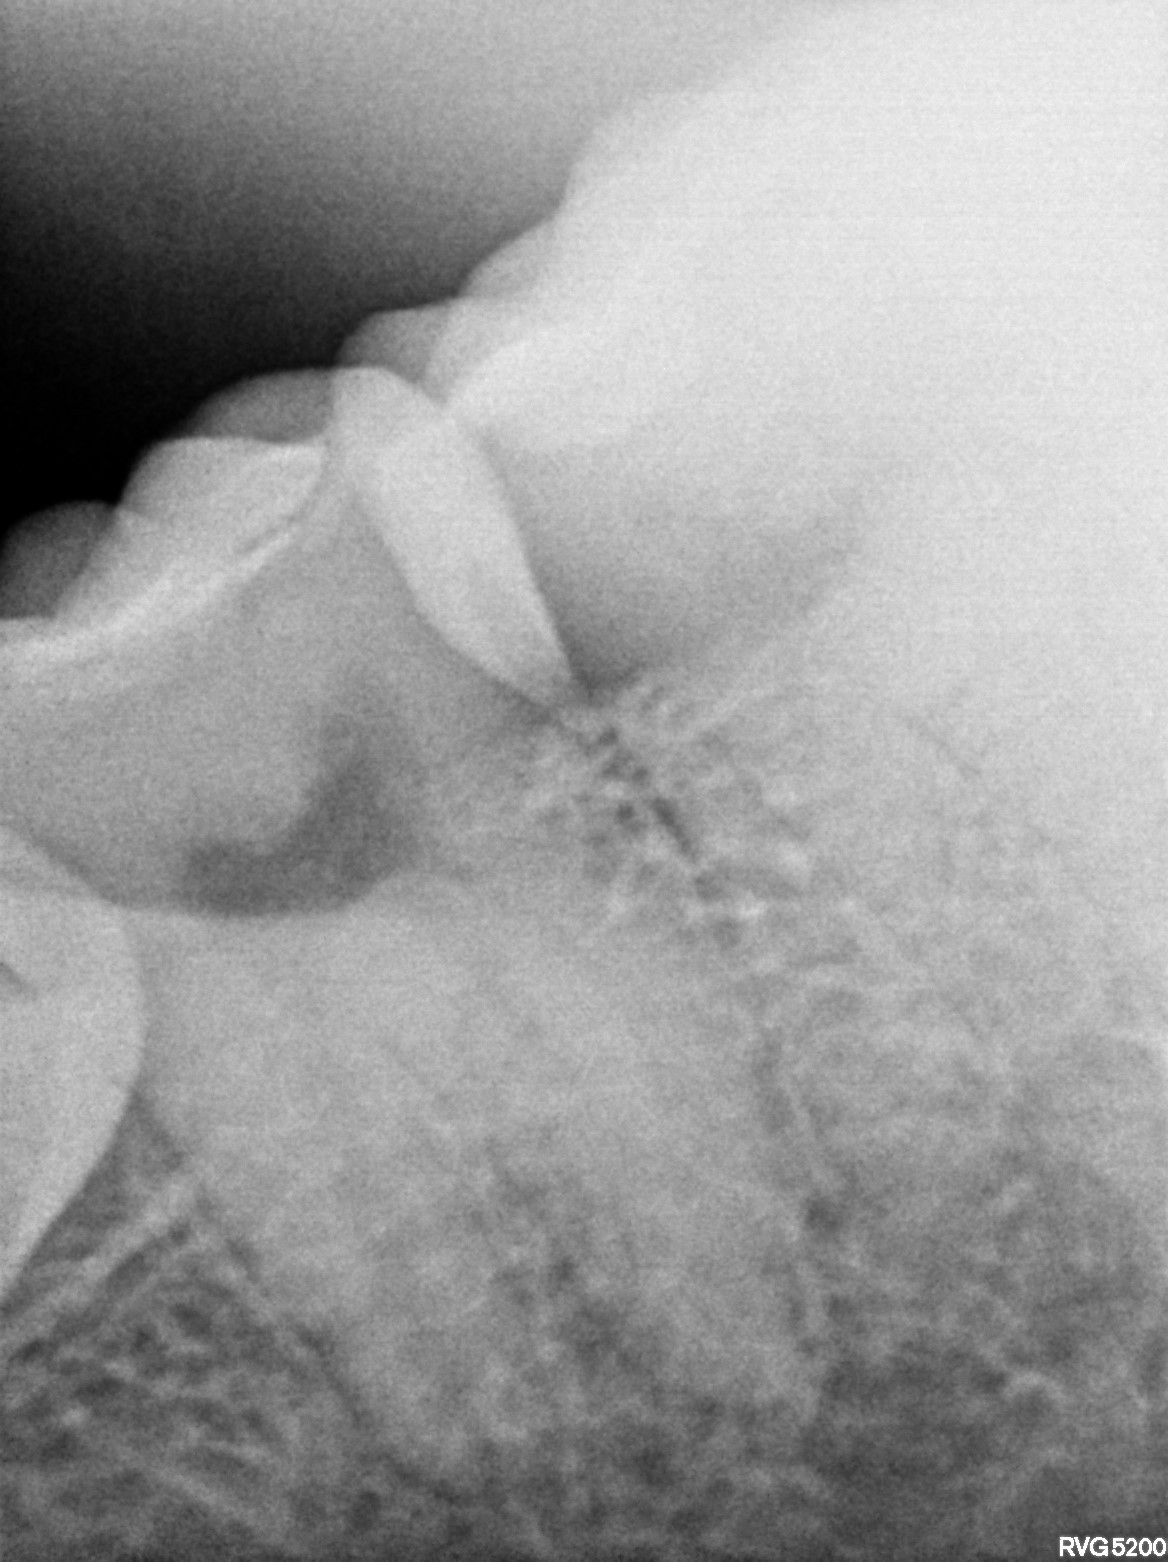

Dental Radiographs FHIR: DocumentReference · LOINC 24641-7

xray_1772899428_1.jpg

24641-7

| Necrosis of dental pulp | K04.1 | 234946006 | resolved | 2026-03-07 | adv rct with 47(5k-5500) followed by ceramic crown 3500 and surgical extn with 38 @7k-8k// extn with 48 advised only if pain persists and if pt wills | |

| Root canal treatment | 234780006 | D3330 Endodontic therapy, molar tooth | ##47, #38, #48 | 2026-03-07 | completed | adv rct with 47(5k-5500) followed by ceramic crown 3500 and surgical extn with 38 @7k-8k// extn with 48 advised only if pain persists and if pt wills | |

| 2026-03-07 21:33 | fulfilled | adv rct with 47(5k-5500) followed by ceramic crown 3500 and surgical extn with 38 @7k-8k// extn with — Dr Hani | |